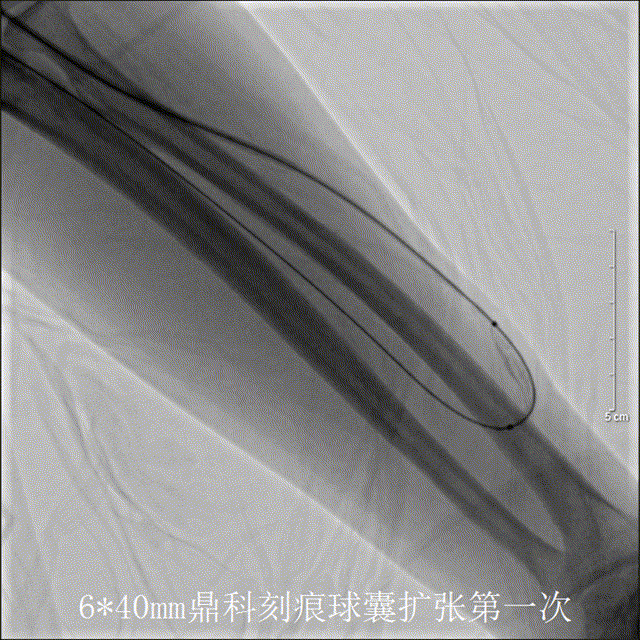

应用6*40mm高压刻痕球囊第一次扩张即见狭窄段轻松扩开